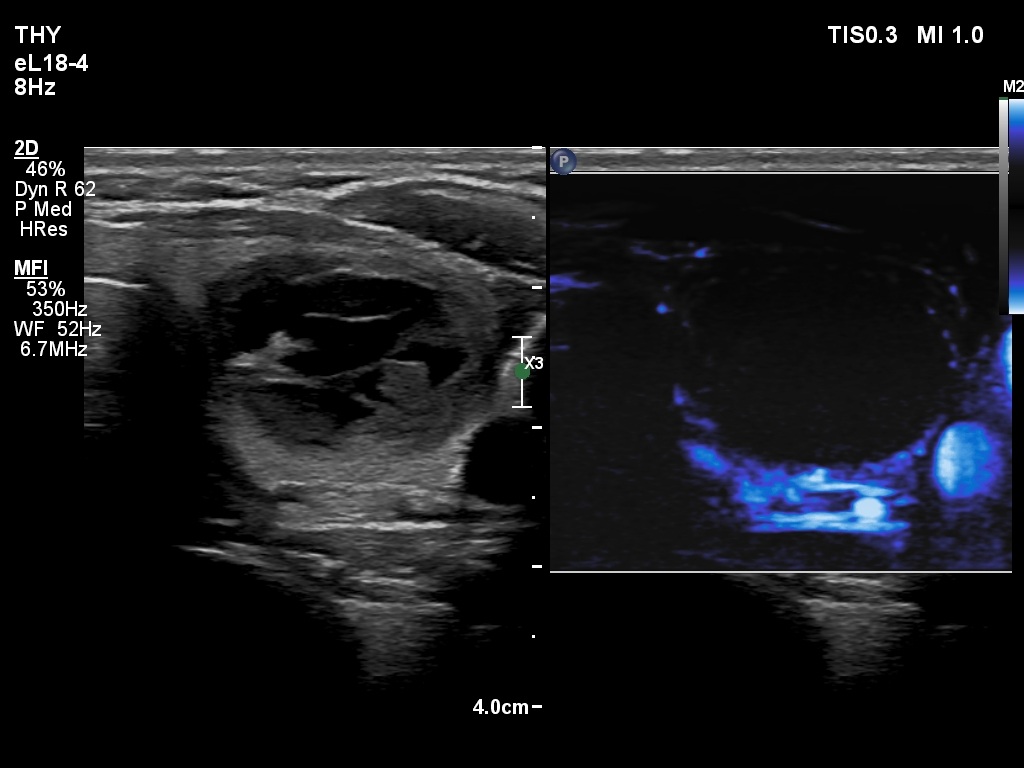

First examination (first and second rows of images)

Clinical presentation: A 39-yr old woman was referred for evaluation of a thyroid cyst which has refilled twice in the past. On the last aspiration, 2 years ago the maximal diameter of the nodule was 24 mm.

Palpation: no abnormality.

Laboratory test: 2.71 mIU/L.

Ultrasonography. The thyroid was echonormal. There was a central-type cystic nodule in the left lobe. The solid portion was echonormal-minimally hypoechoic. The lesion showed back wall cystic figures.Cytology was performed from the lesion in the left lobe and resulted in benign, cystic-colloid goiter.

Suggestion. Ultrasound in two years, in the event of complaints at once. If the cyst would recur ethanol sclerotherapy is advised.